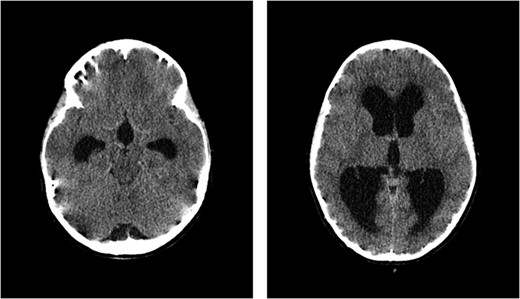

CT scan of the brain showed acute hydrocephalus with massive dilatation of lateral and third ventricles (at mesencephalon and thalamus levels, respectively).